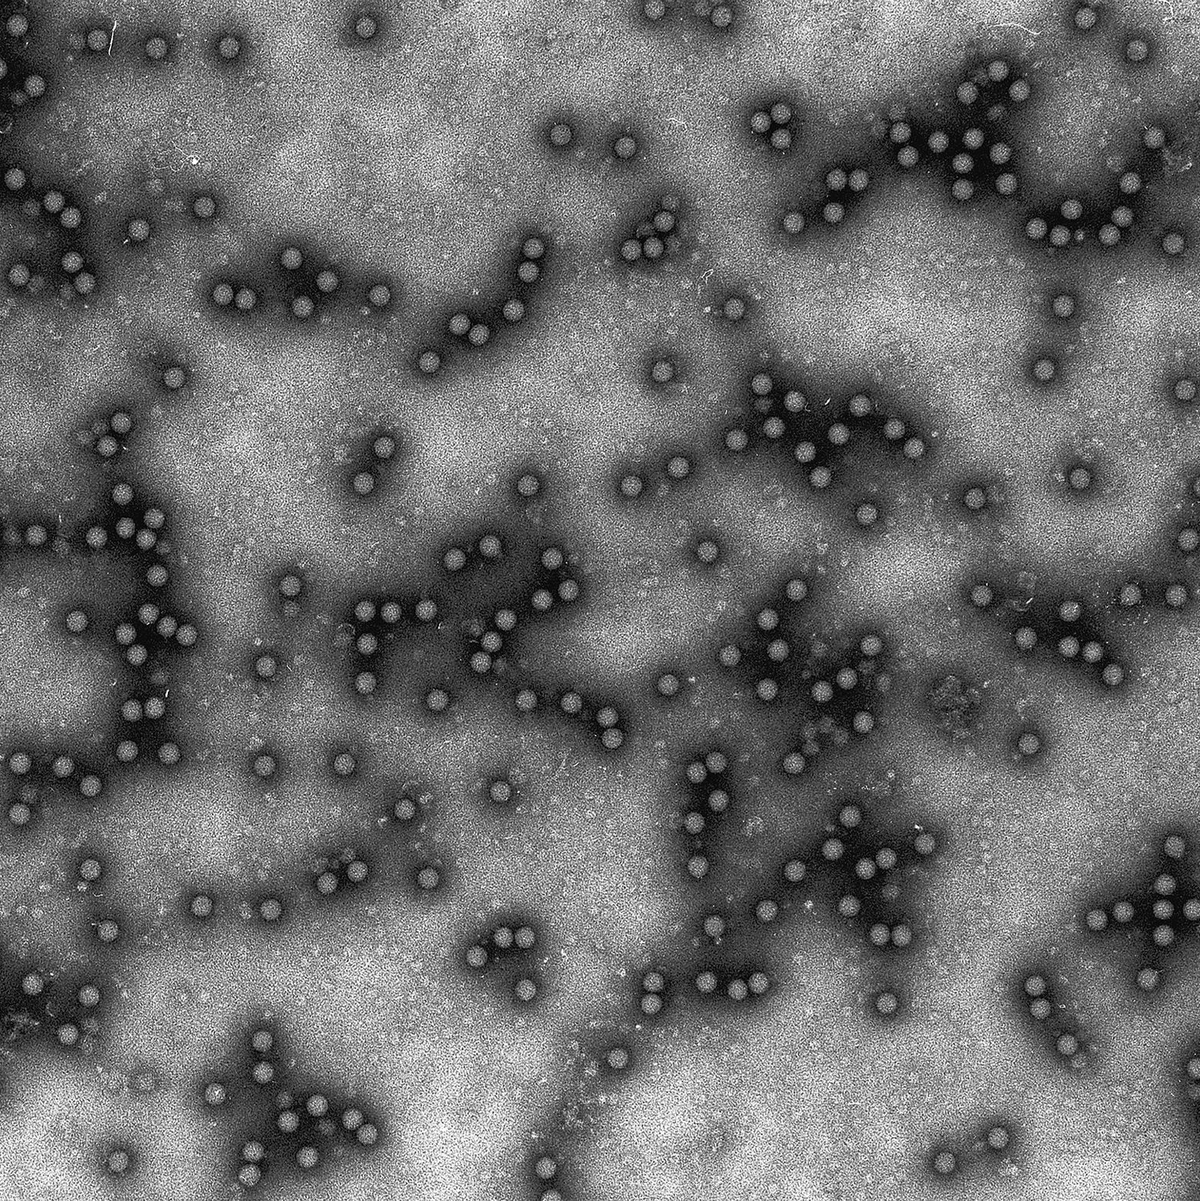

Verursacht wird die Krankheit durch ein Virus. Anstecken können sich vor allem Klauentiere wie Rinder und Schweine, Schafe und Ziegen. Die betroffenen Tiere haben hohes Fieber, starke Schmerzen und lahmen, auĂerdem bilden sich an Zunge und Lippen, an Klauen und Zitzen viele BlĂ€schen.Â

Von der Infektion bis zu den ersten Symptomen dauert es nur zwei bis sieben Tage, deswegen kann sich die Seuche schnell ausbreiten. Tödlich verlĂ€uft sie nur selten, allerdings ist die Sterblichkeit bei Jungtieren höher. Tiere, die genesen sind, bleiben oft geschwĂ€cht. KĂŒhe geben oft kaum noch Milch. Auch können diese Tiere das Virus noch lange Zeit ausscheiden.

Das Virus kann monate- oder gar jahrelang infektiös bleiben, auch wenn es im Erdboden ist oder eingetrocknet. Es kann direkt von Tier zu Tier weitergegeben werden, etwa ĂŒber den Atem, aber es kann sich auch ĂŒber die RĂ€der von Fahrzeugen oder an Schuhsohlen und Kleidung verbreiten. In Deutschland wurde das Virus vor dem aktuellen Fall zuletzt vor mehr als 35 Jahren nachgewiesen. Auch in der ĂŒbrigen EU gab es zuvor seit Jahren keinen bestĂ€tigten Fall.